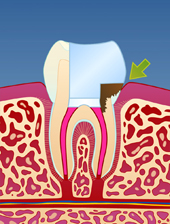

En rotfylt tann er ofte svekket på grunn av store fyllinger og lite gjenværende tannsubstans (fig. I). Som resultat vil en rotfylt tann være mer utsatt for å knekke enn en tann som ikke er rotfylt (fig. II-III). Dersom rotfyllingen blir utsatt for lekkasje over lengre tid, kan bakterier komme til og lage en ny infeksjon i den rotfylte tannen (fig. IV). Der er derfor viktig å kontakte tannlege snarest dersom deler av en rotfylt tann knekker av.

| figur I | | figur II | | figur III | | figur IV |

På samme måte kan et dypt hull i tannen medføre at bakterier kommer

inn til rotfyllingen og infiserer denne på ny (fig. V-VIII). Det er

derfor svært viktig med grundig renhold, også rundt rotfylte tenner.

| figur V | | figur VI | | figur VII | | figur VIII |